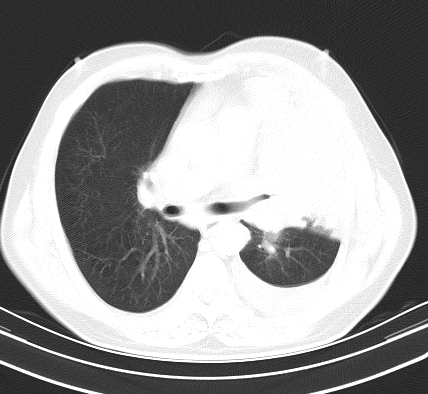

以下是引用老爱克斯新网客在2008-7-31 6:30:00的发言:[br]左肺上叶大片状病灶,左肺上叶支气管狭窄呈鼠尾状,左肺门增大,纵隔内见肿大淋巴结,左侧胸腔积液,余肺清晰。左肺中心型肺癌淋巴结转移,

以下是引用zjb在2008-7-31 6:32:00的发言:[br]左侧中心性肺癌 阻塞性肺炎 肺不张 胸腔积液 建议气管镜

以下是引用zjzjr在2008-7-31 8:45:00的发言:[br]考虑左侧中心性肺癌伴阻塞性肺炎,左肺上叶肺不张,纵隔淋巴结转移;左侧胸腔积液。建议行纤支镜检查。

以下是引用sdzyy在2008-7-31 8:47:00的发言:[br]病灶较治疗前有所进展,胸水增多, 左侧中心性肺癌 并 阻塞性肺炎 肺不张 胸腔积液 可能性大; 建议气管镜检查。 [br] [br]